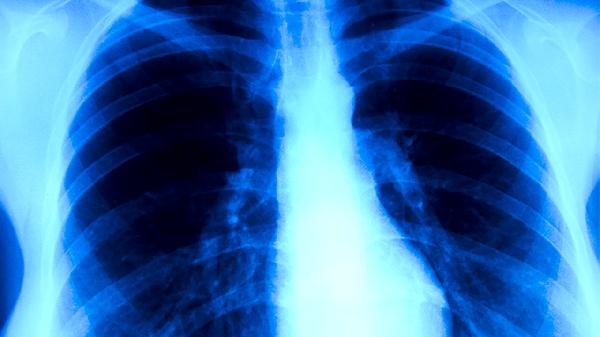

肺结核是由结核分枝杆菌引起的慢性传染病。简单的说,就是肺部出现了结核病变等现象。那么,接下来便来让我们详细介绍一下肺结核丸对肺结核有效果吗?怎么购买肺结核丸?